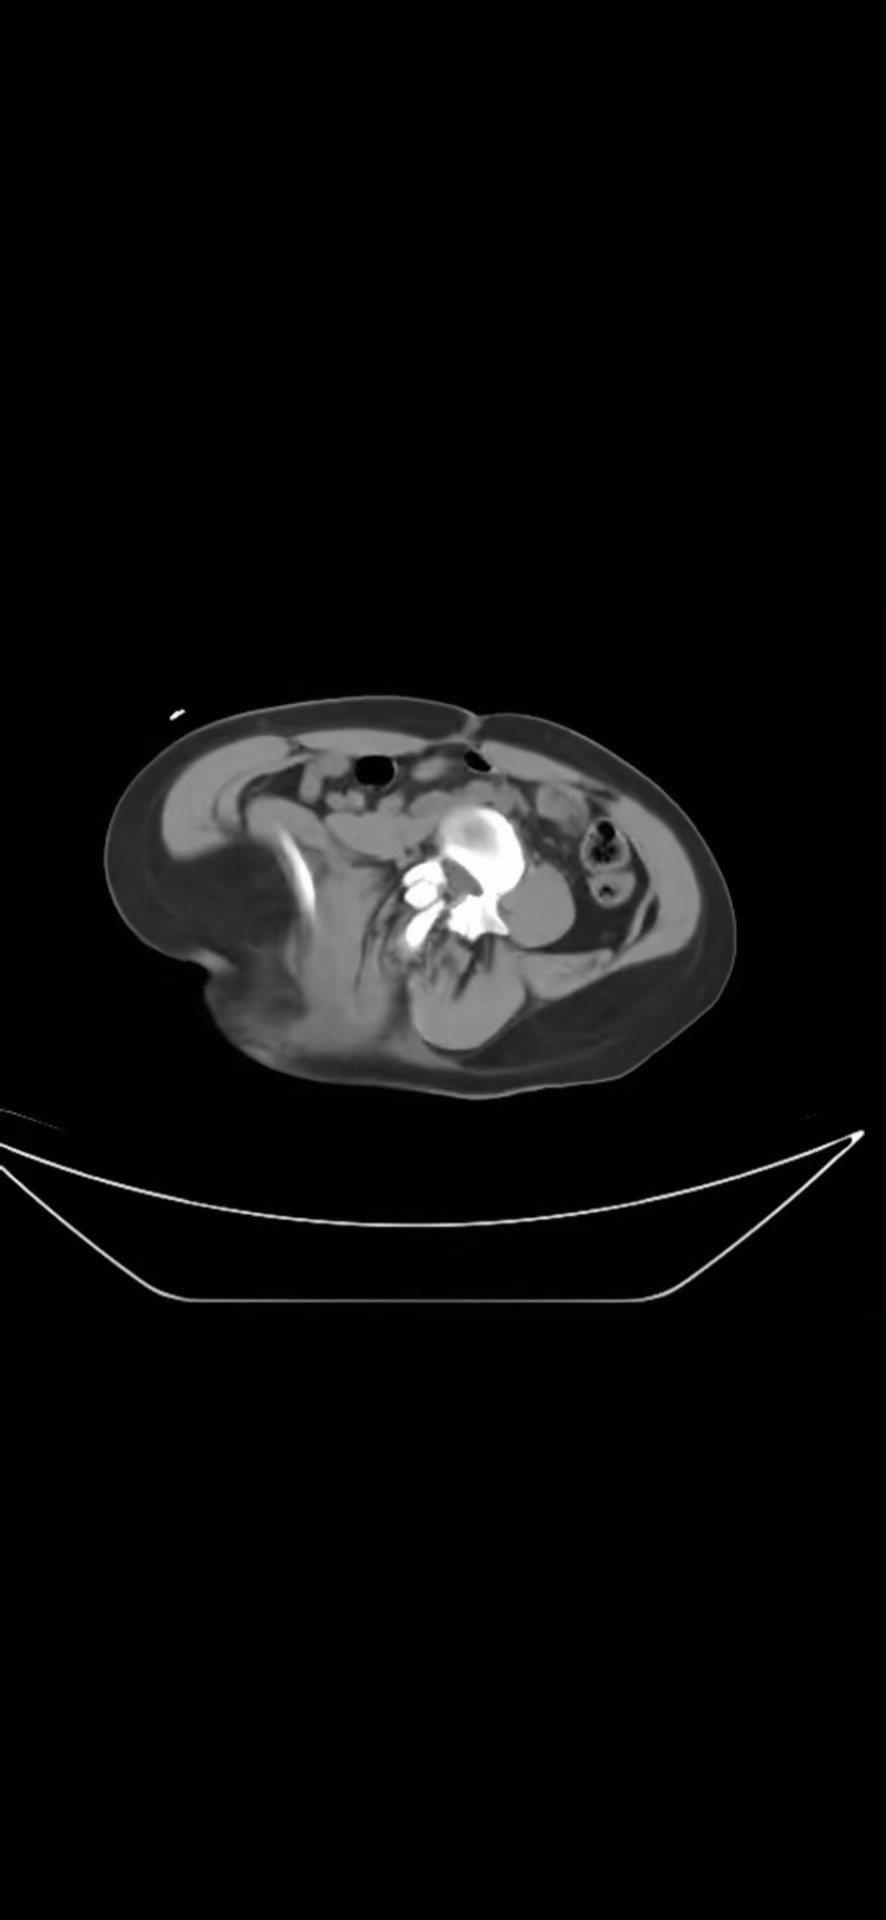

CT平扫: